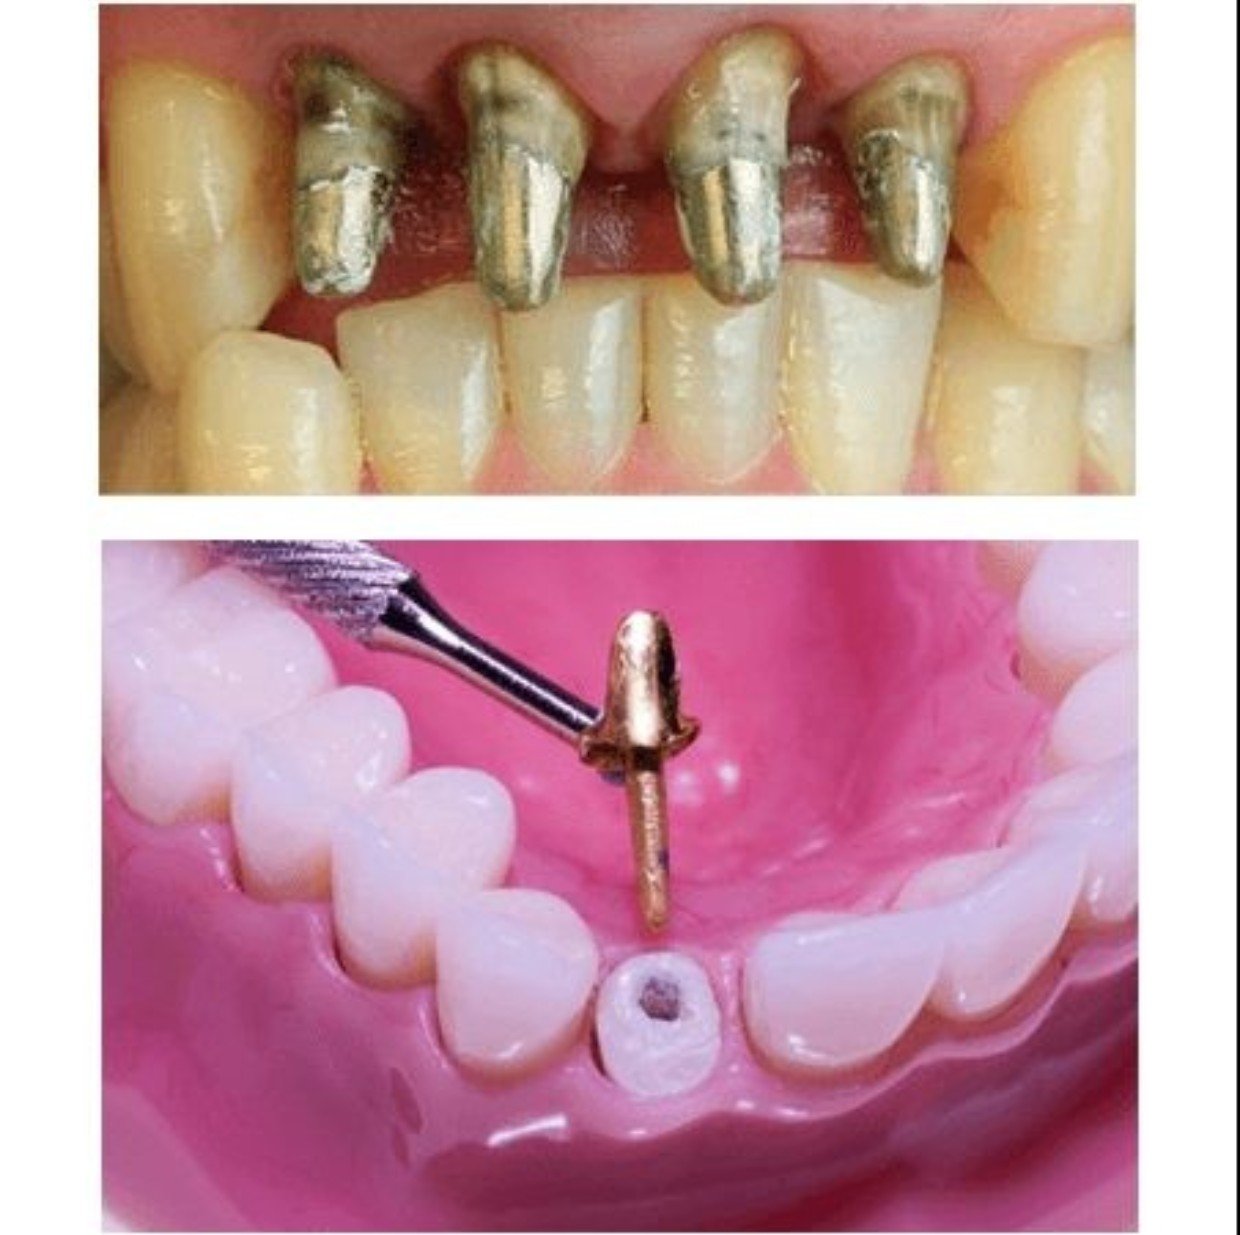

Để bọc răng sứ bác sĩ bắt buộc phải mài răng thật để làm cùi. Sau đó, gắn mão sứ bên ngoài và kết thúc quá trình bọc sứ. Tuy nhiên trong một số trường hợp như: Răng đã điều trị tủy răng nhiều lần, răng bị sâu nặng, men răng bị hư tổn quá nhiều không thể mài cùi răng vì không đủ men răng, thì bác sĩ sẽ tiến hành gắn cùi răng sứ giả.

Tóm lại, cùi răng sứ giả là một dạng mô phỏng của cùi răng thật. Mục đích để răng cứng chắc hơn, tạo trụ đỡ cho mão sứ gắn bên ngoài. Cùi răng sứ giả có thể được làm từ nhiều chất liệu và kích cỡ khác nhau tùy thuộc vào tình trạng răng của mỗi người.

Cùi giả kim loại có cấu tạo gồm hai lớp: khung sườn được làm từ hợp kim Cr – Cb, Cr – Ni hoặc Titan và vỏ sứ Ceramco III. Cùi răng giả kim loại mang lại nhiều ưu điểm như:

Tuy có độ cứng chắc cao và chi phí khá thấp, song cùi răng kim loại vẫn còn nhiều hạn chế. Chẳng hạn như về màu sắc của răng. Bởi do được làm từ kim loại, nên sau một thời gian sử dụng sẽ bị oxy hóa. Gây ra hiện tượng đen viền nướu kém thẩm mỹ.

2.2 Thân răng giả toàn sứ

Khác với cùi răng sứ kim loại, cùi giả toàn sứ được cấu tạo từ 100% phôi sứ nguyên chất. Đây là lựa chọn tối ưu dành cho khách hàng muốn chụp răng sứ thẩm mỹ nhưng cấu trúc răng chưa được đảm bảo. Cùi răng giả toàn sứ mang lại nhiều ưu điểm như: